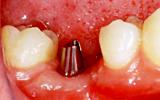

インプラントだと解りますか? | |||||||||||

| インプラント治療技術の進歩によって、自分の歯と殆ど見分けがつかないように治療することが可能になりました。しかし、インプラントは決して自分の歯にまさる物ではありません。まず、ご自分の歯を大切にして下さい。 | ![]() |

【術前】 |

【術後】 |